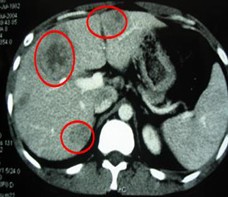

患者情況:肝細(xì)胞性肝癌,術(shù)后復(fù)發(fā),右肝內(nèi)多個(gè)病灶。治療方案:瘤內(nèi)注射今又生1×1012VP/次/周,共8周,同時(shí)聯(lián)合肝動(dòng)脈化療栓塞(TACE),1次/月,共2次。下圖示:左側(cè)上下兩圖為治療前,CT示血管豐富;右側(cè)上下兩圖為治療一個(gè)療程后,碘油均勻沉積,腫瘤血供減少。

治療前

治療后